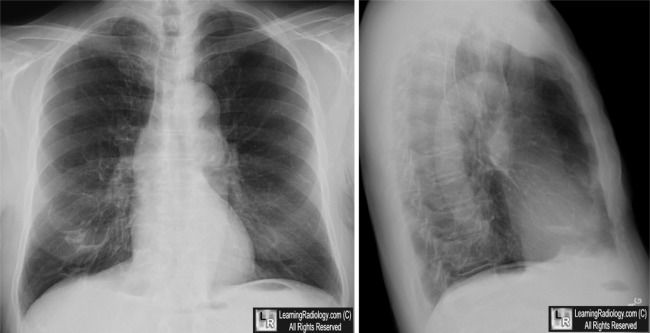

图3 囊状支气管扩张:CT,可见支气管明显扩张,一些可见气-液平面(黄色箭头),大部分位于右肺。胸部X线片:显示右下叶薄壁的囊状影(白色箭头),部分可见气-液平面(黄色箭头)。医脉通编译整理自:http://learningradiology.com/index.htm